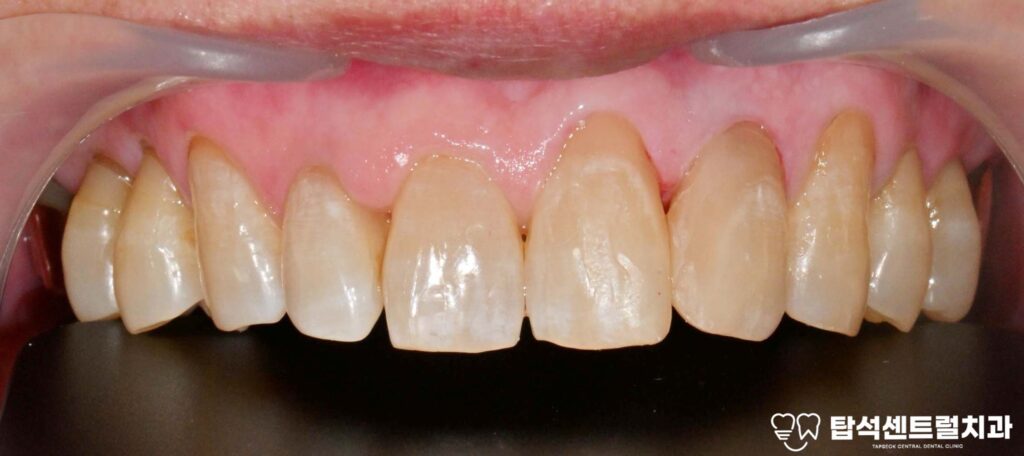

벌어진 앞니 부위 결과와 관리 방법 소개

벌어진 윗니 사이 부분을 메운 후에는

자연스러운 형태로

회복되는 것을 확인할 수 있습니다.

발음 개선과 식사 기능 향상,

심미적 만족도가 높아지기를

기대할 수 있습니다.